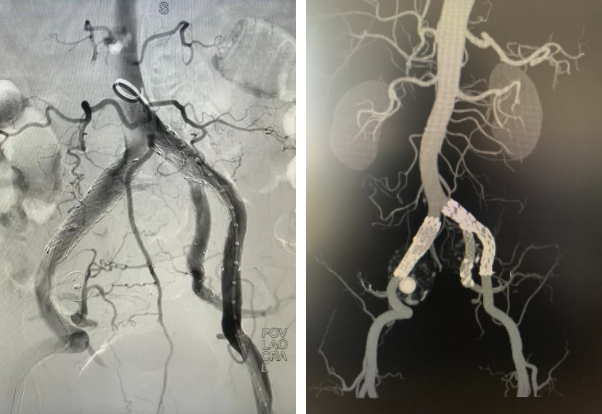

面对挑战,消化内科团队迅速启动多学科会诊。由血管外科驻桂专家王伦常博士、姚松良副主任医师及陈国兴硕士组成的攻坚小组,经全面评估后,决定优先通过微创手术处理动脉瘤。为了不影响后续的结肠手术,团队创新性地采用了PMEG技术,在局部麻醉下为患者施行了左侧髂内动脉瘤隔绝并重建术。术中,团队对支架进行了精准的台上改造与开窗,不仅成功隔绝了瘤体,更完美重建了左侧髂内动脉,保住了至关重要的血液供应。术后,患者恢复顺利,及时转入普外二病区(胃肠外科)完成了结肠肿瘤的治疗,现已康复出院。

术中团队对支架进行精准的台上改造与开窗

手术为患者完美重建左侧髂内动脉

心脏问题解决后,治疗的“接力棒”交到了血管外科团队手中。团队预先在腹主动脉支架上为副肾动脉开窗并标记,随后在术中精准定位,将导丝导管通过开窗口超选入副肾动脉并成功植入支架,最终造影显示,腹主动脉瘤被完全隔绝,副肾动脉血流通畅,且无内漏。术后,患者肾功能维持良好,平安出院。

患者术前、术后DSA检查结果对比